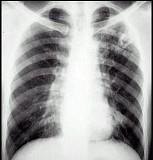

问题 男性,18岁,发热1个月,体温37.538.5℃,抗感染治疗无好转,消瘦明显,胸片见图,最可能的诊断是 ( )

选项 A.肺门淋巴结核 B.淋巴瘤 C.结节病 D.肺癌,淋巴结转移 E.原发性肺结核

答案 E